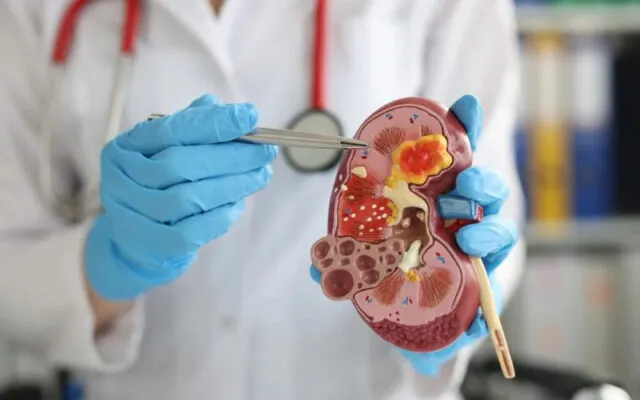

Các phương pháp chữa sỏi thận ở Singapore

Sỏi thận là một bệnh lý phổ biến gây ra nhiều đau đớn và ảnh...

Nang thận: Hiểu rõ để bảo vệ sức khỏe

Nang thận là gì? Bạn có từng nghe đến thuật ngữ này chưa? Đừng quá...

U nang thận: Chẩn đoán và điều trị hiệu quả

Sức khỏe của hệ tiết niệu luôn cần được quan tâm đúng mức, đặc biệt...